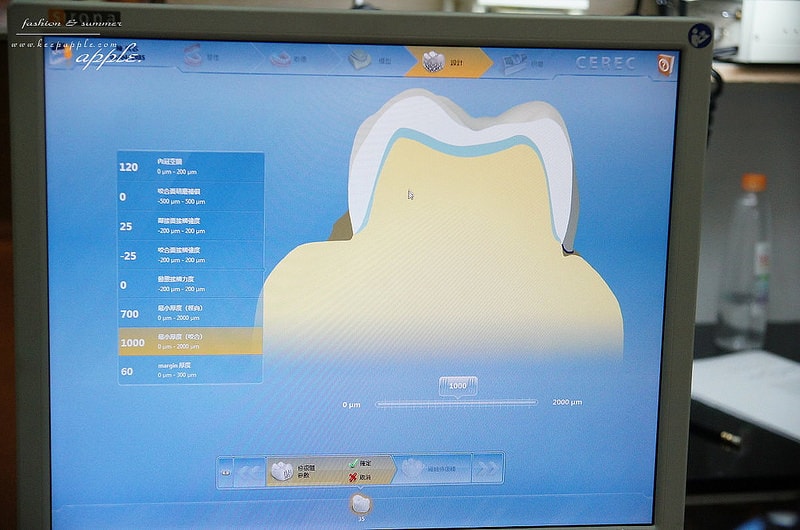

就是用超厲害的數位化口內掃瞄機進行掃描啦!

持續掃描大約三到五分鐘的時間

就可以把整個口腔的牙齒及牙肉組合成3D影像

居然還可以360度翻轉喔!

這台機器真的很厲害,甚至很多大醫院都還沒有引進

口掃完成之後

資料會傳輸到所有的資料會連動到

>>「3D全瓷冠4軸快速研磨機」上面

當場就可以把假牙研磨出來囉!